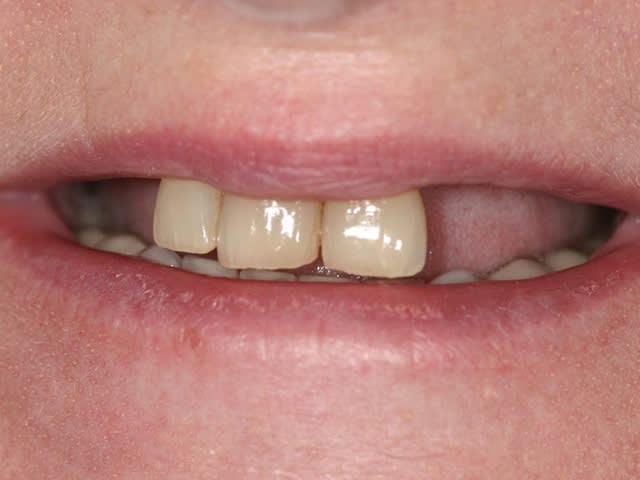

bon, toujours aussi speed je suis, mais après certaines réclamations, et malgrès ma réticence à poser un cas non "consolidé", voici en avant première mon premier all on 4, version photos ratées et non retouchées, mais... speed je suis je vous disais ;)

sto le bla bla, et pasons le diaporama... bon voyage au pays de la mise en charge immédiate totale au maxillaire de fille carole sur dame ginette, une patiente en or que j' adore, et pour qui je suis très très heureuse d' avoir pu réaliser cette chirurgie et la première étape prothétique.....